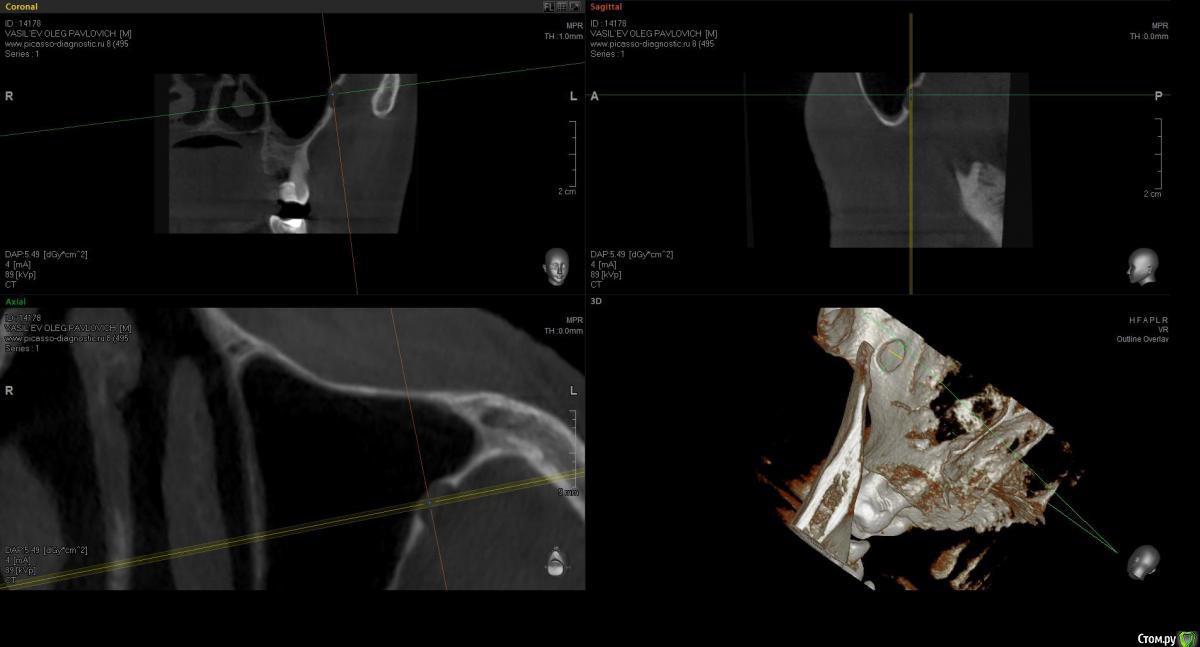

sugaka30 Опубликовано 7 января, 2017 Автор Поделиться Опубликовано 7 января, 2017 (изменено) Сделал Кт Может кто прокоментирует Не пора ли мне Пора? А то что то мне все плохеет https://yadi.sk/d/RXxAPdk237XVpi Заранее спасибо Изменено 7 января, 2017 пользователем sugaka30 Ссылка на комментарий

sugaka30 Опубликовано 7 января, 2017 Автор Поделиться Опубликовано 7 января, 2017 И скажите все таки есть перфо материала в гайморову или пронесло? Ссылка на комментарий

sugaka30 Опубликовано 22 января, 2017 Автор Поделиться Опубликовано 22 января, 2017 Проконсультируйте пожалуйста по этим срезам А то местный хирург не может понять что не так Ссылка на комментарий

St. Опубликовано 22 января, 2017 Поделиться Опубликовано 22 января, 2017 Скрины кт в обл леченного зуба Ссылка на комментарий